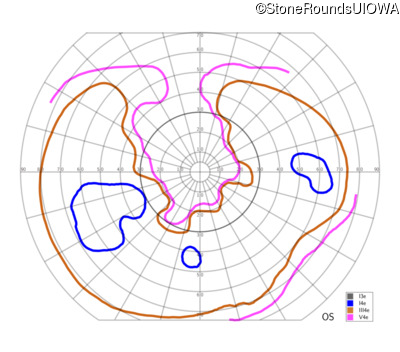

The clinical features supporting the diagnosis of Bardet Biedl syndrome in this patient include: bone-spicule-like pigmentation, narrowed arterioles and macular atrophy on ophthalmoscopy; photoreceptor loss on OCT; ulnar polydactyly, obesity, abnormal cognition, hypertension; and, normally sighted parents.